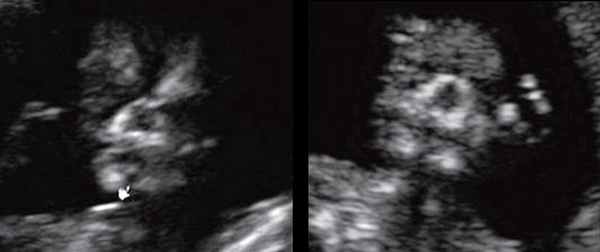

Для качественной оценки особенностей строения нижней челюсти в I триместре беременности специалистами МГО МОНИИАГ совместно с профессором W. Sepulveda (Чили) был изучен и впервые описан новый ультразвуковой признак нижнечелюстной промежуток (mandibular "gap"), визуализируемый при первом скрининговом ("генетическом") ультразвуковом исследовании [18, 19].

Методика базируется на изучении коронарного скана лица плода, так называемого ретроназального треугольника, при котором визуализируется верхняя и нижняя челюсть. Техника получения этого скана чрезвычайно проста и может быть рекомендована для скринингового исследования в 11-14 нед беременности. Эта методика позволяет оценить нижнюю челюсть плода без применения трудоемких оценок, и не сопряжена с математически сложными расчетами коэффициентов, также она существенно не увеличивает время осмотра. Коронарный скан можно оценивать как в режиме 2D, так и в режиме объемной эховизуализации 3D. Методика оценки коронарного скана лица плода в I триместре беременности показана на рисунке 6.

Рис. 6. Методика оценки коронарного скана лица плода в I триместре беременности.

Обе ветви нижней челюсти при сроке 11-14 нед беременности выглядят гиперэхогенными, а в месте слияния имеют характерный гипоэхогенный промежуток, ультразвуковой "разрыв". Этот признак визуализируется при нормальном развитии нижней челюсти (mandibular "gap").

Размер этого промежутка уменьшается с увеличением срока беременности. Нижнечелюстной промежуток здорового плода представлен на рисунке 8.

Рис. 8. Нижнечелюстной промежуток в 13 нед беременности при нормальном развитии нижней челюсти.

При патологии нижней челюсти (микрогнатии) в срок 11-14 нед беременности при изучении коронарного скана лица нижнечелюстной "промежуток" отсутствует, нижняя челюсть представлена единой, слившейся костной массой. Отсутствие нижнечелюстного "промежутка" (mandibular "gap") при эхографии в этот срок является маркером гипоплазии нижней челюсти (микрогнатии). Варианты отсутствия нижнечелюстного промежутка при микрогнатии при различных синдромах в срок 11-14 нед беременности представлены на рисунке 9.

Рис. 9. Отсутствие нижнечелюстного промежутка при микрогнатии, при различных синдромах нехромосомного генеза в 11-14 нед беременности.